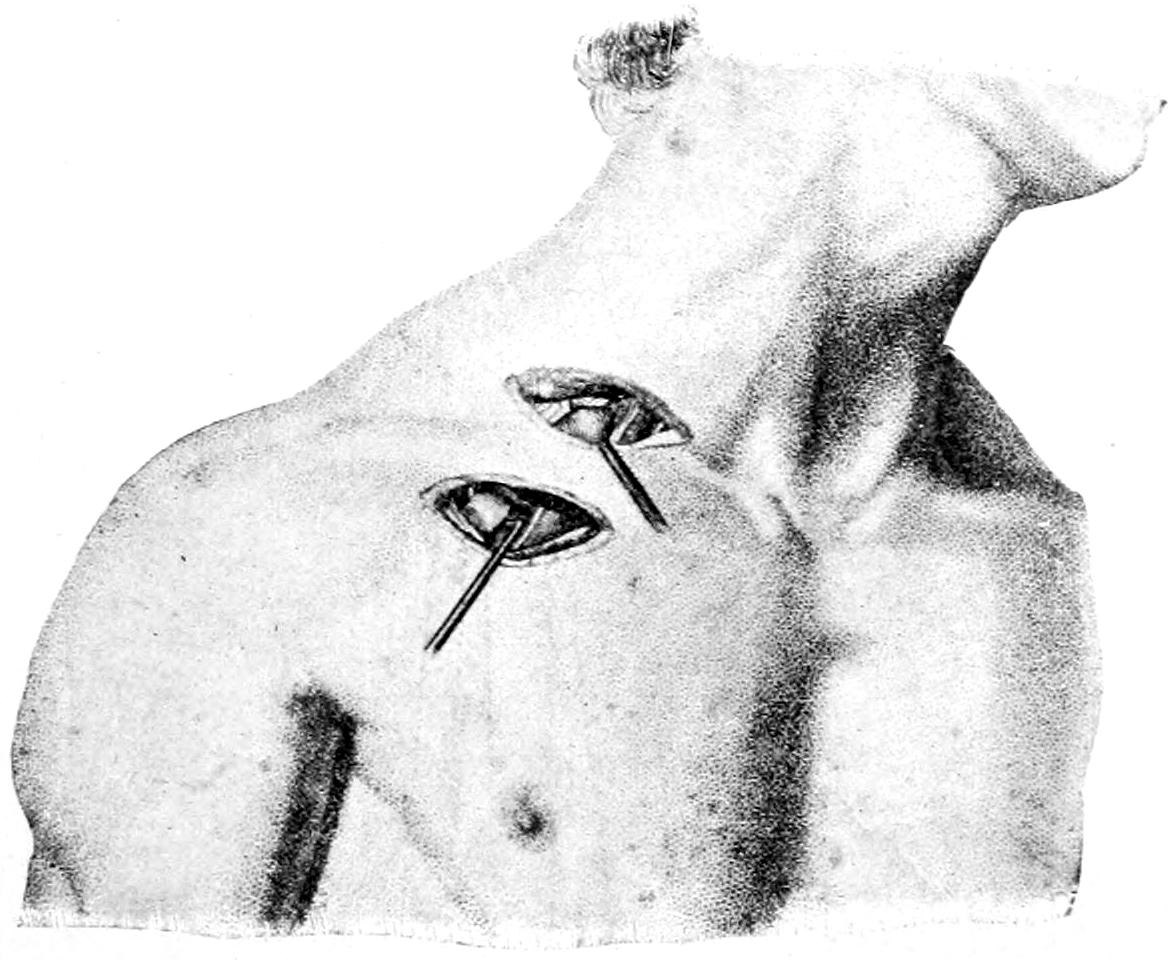

CHAPTER XLIII.

THE THORAX AND ITS CONTENTS 718